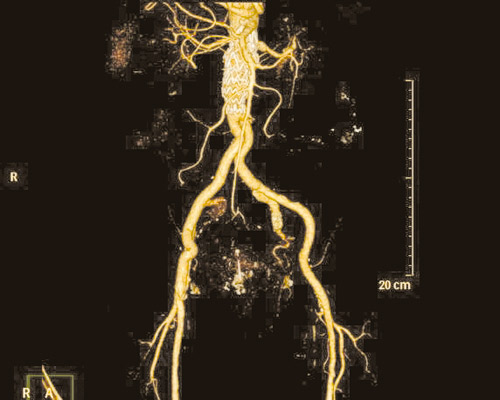

نجح فريق الأشعة التداخلية بالتعاون مع قسم جراحة الأوعية الدموية في إجراء عملية لإصلاح الشريان الأورطي عن طريق تركيب دعامات بواسطة القسطرة التداخلية «إيفار» عن طريق فتحة صغيرة في الجلد. ويعتمد الأسلوب الجديد على تصليح التمدد بالشريان الأورطي عن طريق تركيب دعامة صناعية من خلال قسطرة يتم إدخالها من شرياني الفخذين مما يعجل بالشفاء وتقليل المضاعفات الجراحية والنزيف ومدة البقاء تحت الرعاية المركزة خاصة لبعض الحالات التي لاتسمح حالتهم البدنية والصحية بالتخدير فضلا عن اختصار زمن وتكلفة العلاج مقارنة بالعمليات الجراحية التقليدية. حيث كان يتم في السابق أجراؤها عن طريق الشق الجراحي وما يعقبه من آلام شديدة للمريض ومضاعفات جانبية وطول فترة البقاء في المستشفى.